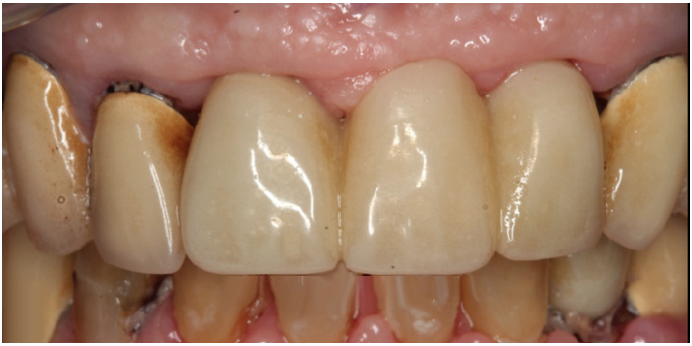

Figure 3 shows a ti-base connection, narrow emergence profile of the zirconia abutment (pink characterization), and final abutment with margins that were computer-generated and computer-manufactured to reflect the appropriate soft-tissue architecture for the patient. As shown in Figure 4, the abutment was seated and torqued to 25 Nm, allowed to rest for 10 minutes, and torqued once again to 25 Nm. The crown was tried in, fit was verified, and occlusion was established. This particular patient was concerned that the implant crown and implant would not look natural. Before beginning the single-tooth replacement with implant dentistry, a diagnostic wax-up and photographic imaging were employed to help develop a natural-looking provisional during the osseointegration phase. A treatment plan was developed and presented to the patient for considering cosmetic dentistry for tooth Nos. 6 through 11. The patient was still apprehensive and chose to begin therapy for only tooth No. 8. Since the final seat date, the patient has been very satisfied with the results of the single-tooth therapy and has committed to completing the cosmetic dentistry services for tooth Nos. 6 through 11.

Fig 3. 0 degree, milled characterized hybrid zirconia abutment with a Ti-base connection. Note the narrow emergence profile of the zirconia

abutment (pink characterization) and final abutment with margins that were computed-generated and computer-manufactured to reflect the

appropriate soft-tissue architecture.

Figure 3

Fig 4. Seated abutment (left) and crown try-in (right).

Figure 4